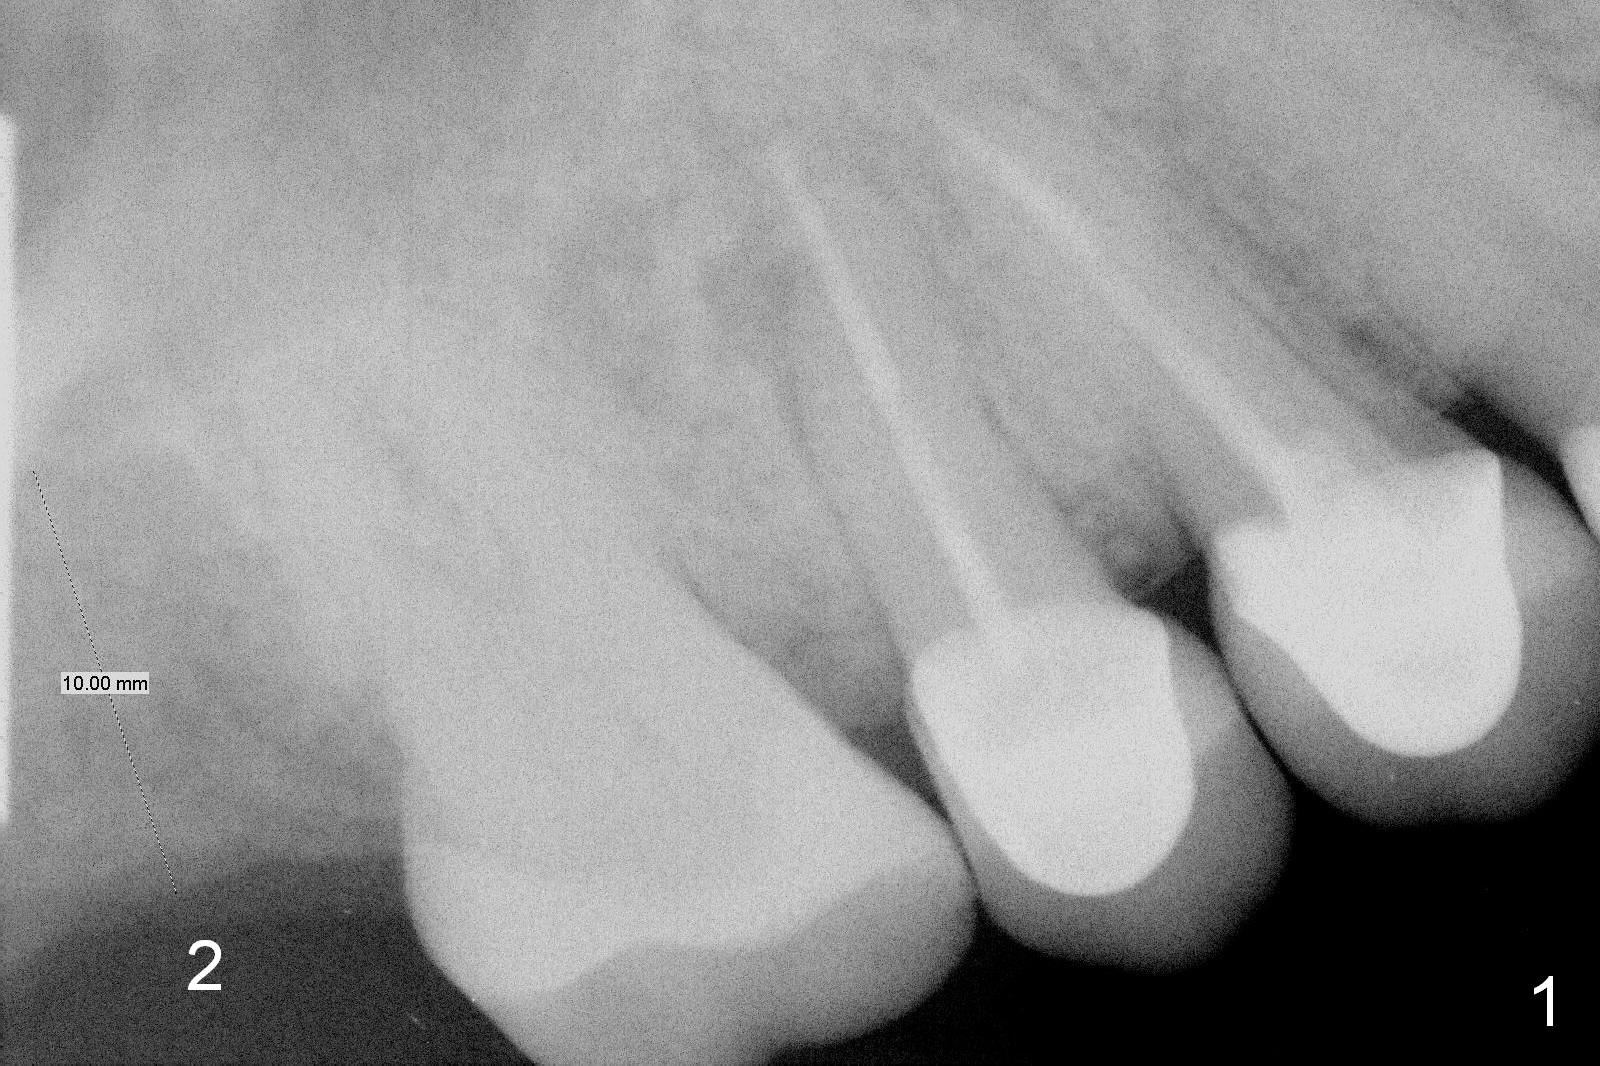

Bone Expansion, Sinus Lift and Deep Implant Placement

A 60-year-old woman has lost the tooth #2 for a few years (Fig.1). Since then, three of her anterior teeth have fractured and required implant placement (#8, 10,11). It appears that restoration of the tooth #2 may alleviate further anterior breakdown. There are 2 challenges associated with this case: supraeruption of the opposing teeth and low bone density (40-200).

To tackle the 1st challenge, place an implant as deep as possible and reduce the opposing tooth as early as possible (immediately after implant placement with immediate provisional if possible).

To handle the 2nd challenge, start bone expansion with #15 and osteotomes (from 8 to 11 mm). Set implant spacer at 4 mm (Fig.2). Prepare allograft (.5-1 mm) and Osteogen (4:1 ratio) for sinus lift. Place 8 mm stopper on the larger condenser from Sinus Master Kit.